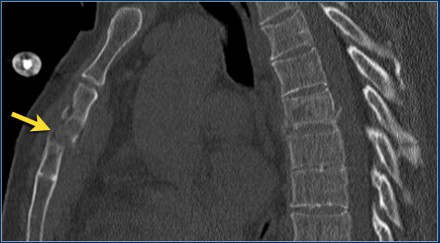

The images are of a patient with a typical bamboo spine as a result of ankylosing spondylitis.

After a fall on his back no fracture was seen on the x-rays.

However the CT shows a thin fracture line through the anterior side of the vertebral body and also through the spinous process.

Continue with the MR-images.

Look at the images.

The findings are:

- Vertebral bodies show marrow edema as a result of a fracture.

- Torn flaval ligament (yellow arrow).

- Fractures through the posterior elements (red arrows).

The TLICS-score is high, because there is distraction and injury to the PLC.